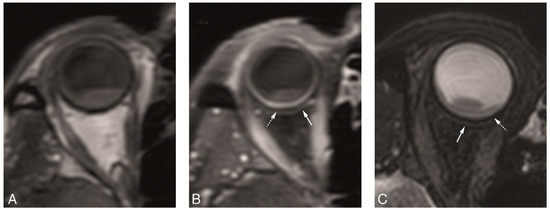

4.2. Anatomical MRI of Uveal Melanoma